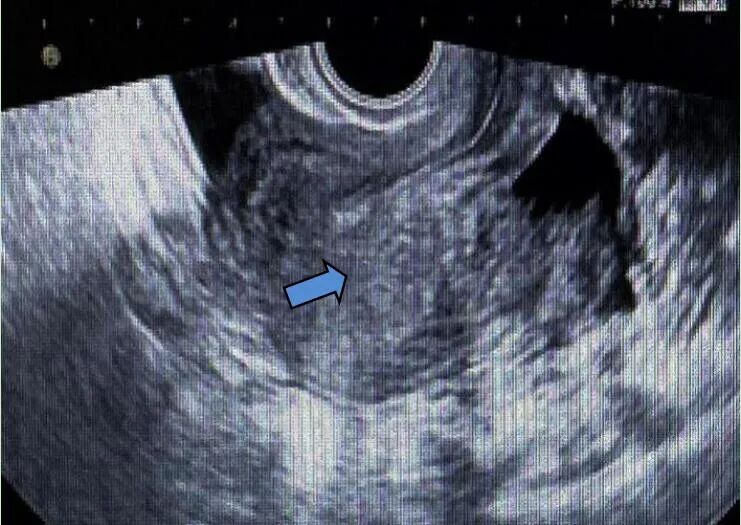

第二次手术后3个月,复查超声见子宫体大小约6.4 cm×6.5 cm×6.1 cm,子宫后壁肌层回声不均质,内见非均质回声,范围约5.2 cm×4.4 cm×3.9 cm,内见不规则暗区,较大范围约1.1 cm×1.1 cm×0.8 cm;CDFI内见点状血流信号,宫腔居中。考虑子宫肌瘤二次复发,因患者年轻、未生育,予GnRHa治疗3个月。

距离第二次手术后8个月,复查超声见子宫体大小约6.2 cm×9.6 cm×4.1 cm,肌层回声不均质,后壁可见囊实性回声,范围约8.6 cm×6.4 cm×4.8cm,略压向宫腔,内见不规则暗区,范围约分别为1.3 cm×1.2 cm×0.6 cm、1.2 cm×1.6 cm×0.4 cm;CDFI示周边及内部均可见条状血流信号,宫腔居中。

第二次手术后10个月,复查超声见子宫体大小约5.6 cm×6.6 cm×5.7 cm,肌层回声不均质,右后壁贴近宫腔并大部外突,非均质回声,范围约9.2 cm×7.6 cm×8.8 cm,内见暗区,大小约7.1 cm×5.5 cm×3.4 cm,内见细密点状回声;CDFI示非均质回声,周边可见条形血流信号,宫腔居中。肿瘤标志物CA125为236.5 U/ml。